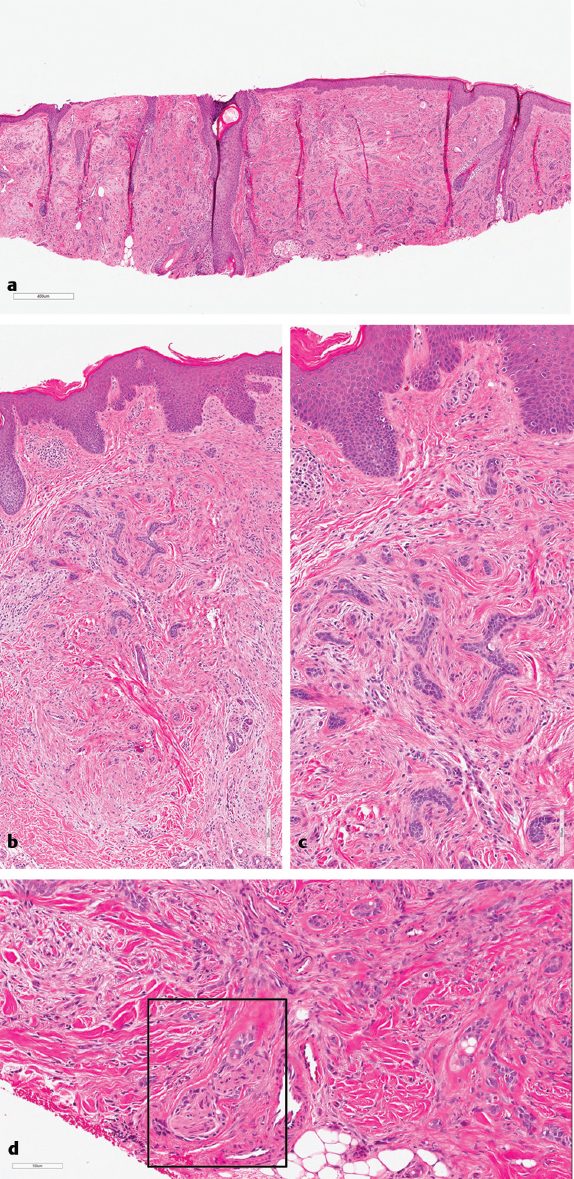

Fig. 11.2a), infiltrative (

Fig. 11.2b, c), and morpheaform (

Fig. 11.2d) subtypes of BCC are associated with a higher incidence of positive margins and thus tumor recurrence.5,6 For this reason, BCC subtyping is important information to be included in the pathology report. The micronodular pattern shows small tumor nodules (< 0.15 mm) and lacks circumscription. Micronodular BCC (

Fig. 11.2e) usually shows at least focal retraction artifact, stromal mucin, increased mitosis, and a lack of papillary mesenchymal bodies, as distinguishing factors from trichoepitheliomas (

Fig. 11.3a–c). Infiltrative BCCs show thin, linear basaloid tumor strands growing in an infiltrative pattern. When the same type of growth becomes even more spiked and associated with a densely sclerotic stroma, tumors are called morpheaform BCC. Perineural invasion is another important pathologic prognostic feature in BCC, and BCC tumors with this feature (

Fig. 11.3d) have higher rates of recurrence and morbidity. While studies on treatment protocols in this setting are relatively limited, Mohs surgery appears to confer better outcome, and adjuvant radiotherapy may be considered.7